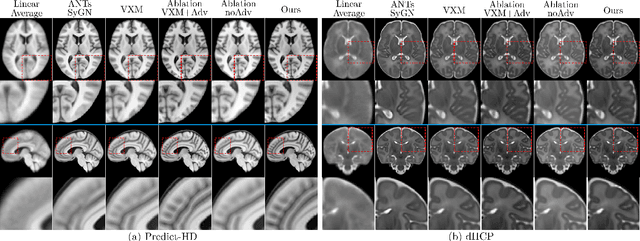

Deformable templates are essential to large-scale medical image registration, segmentation, and population analysis. Current conventional and deep network-based methods for template construction use only regularized registration objectives and often yield templates with blurry and/or anatomically implausible appearance, confounding downstream biomedical interpretation. We reformulate deformable registration and conditional template estimation as an adversarial game wherein we encourage realism in the moved templates with a generative adversarial registration framework conditioned on flexible image covariates. The resulting templates exhibit significant gain in specificity to attributes such as age and disease, better fit underlying group-wise spatiotemporal trends, and achieve improved sharpness and centrality. These improvements enable more accurate population modeling with diverse covariates for standardized downstream analyses and easier anatomical delineation for structures of interest.